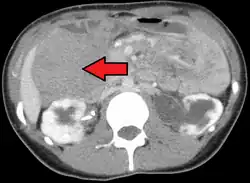

- Tomografia komputerowa

Tomografia komputerowa (TK) jest przydatnym narzędziem w diagnostyce guza desmoidalnego. Pozwala rozpoznać obecność litego guza w obrębie tkanek miękkich, określić jego lokalizację i rozmiar[5]. Jest pomocną metodą w diagnostyce powikłań guza związanych z jego lokalizacją[50]. W tomografii komputerowej guz desmoidalny jest słabo widoczny, ponieważ guz jest izodensyjny lub lekko hipodensyjny względem mięśni. Zmiana ze względu na bogate unaczynienie naczyń włosowatych ulega wzmocnieniu kontrastowemu[50][51]. Ze względu na inwazyjny wzór wzrostu marginesy zmiany mogą być słabo odgraniczone[50].